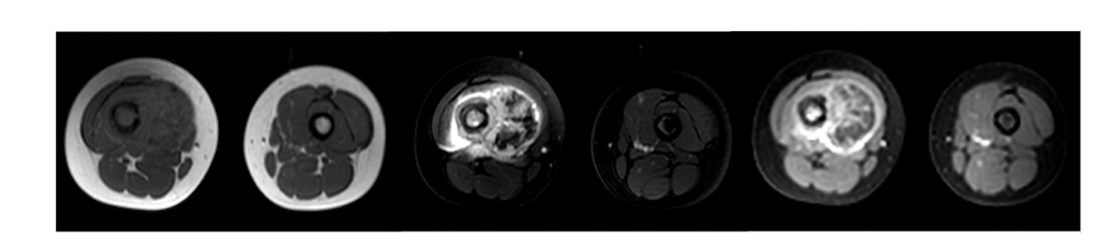

What are the sequences and what is the pathology?

• T1, STIR, T1FS C+

• Tissue lipoma- benign tumour made of fat tissue